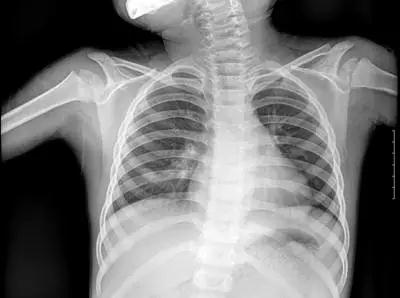

▲X射線成像圖

骨骼、鈣化灶、體內(nèi)液體等(聽(tīng)起來(lái)質(zhì)地較厚重的組織),吸收X光較多,因此形成白色影像,也就是傳說(shuō)中的“高密度影”,上圖的上臂、肋骨就是如此。呼吸道、胃腸道、脂肪組織(聽(tīng)起來(lái)質(zhì)地較疏松),吸收X光較少,在片子上呈現(xiàn)黑色影像,即“低密度影”,圖中含氣體較多的肺臟是代表。再就是密度居中的實(shí)質(zhì)器官、肌肉、結(jié)締組織,比如心臟,在片子上呈現(xiàn)的影像介于黑白兩色之間。X光片“涇渭分明”的特點(diǎn)幫醫(yī)生辨別身體的不同病變。骨折、肋骨病變,密度高的骨骼白色影像哪里出問(wèn)題一目了然,比如液氣胸等肺部及氣道病變,肺臟的黑色影像中就會(huì)混入明亮的白色。